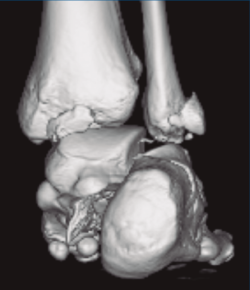

Figura 3. Desplazamiento entre fragmento anteromedial (sustentaculum tali) y posterolateral (tuberosidad).

Se trata de un varón de 19 años que ingresa en reanimación tras precipitarse desde una altura de aproximadamente 10 metros. El paciente presenta una fractura estallido de L3 con afectación del canal medular junto con una fractura del vértice inferior de L4, así como una fractura luxación de calcáneo, asociada a una fractura del maléolo peroneo y del maléolo tibial posterior (Figuras 1 a 6) diagnosticadas mediante TC total body (por eso no se dispone de radiografías simples al momento del ingreso). Como podemos comprobar, se trata de una fractura de doble trazo de tipo hundimiento/depresión de la carilla articular (Figuras 5 y 6).

Figura 4. Luxación fragmento posterolateral.